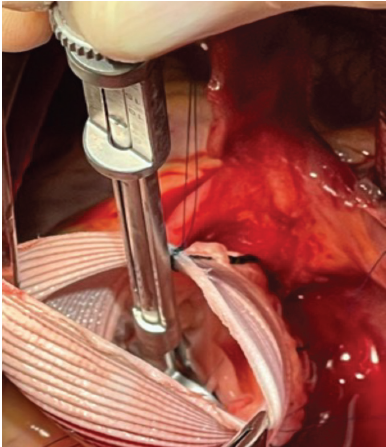

Se aseguraron los postes comisurales dentro del injerto y se realizó la prueba de succión antes mencionada para valorar la coaptación valvular. Posterior a determinar una geometría óptima, se ataron las suturas en el exterior del injerto 10,12. Para reimplantar la válvula, se realizaron dos líneas de sutura. Primero, una forma continua para los tres senos, comenzando por el izquierdo y dejando de último el no coronariano. La segunda línea fue con suturas de colchonero para minimizar el riesgo de sangrado. Estas se realizaron de manera horizontal a lo largo de la línea de sutura de cada cúspide 12. (Figura 1)

Figura 1 Fotografía de campo quirúrgico. Se observa la válvula aórtica reimplantada dentro del conducto de Dacrón.